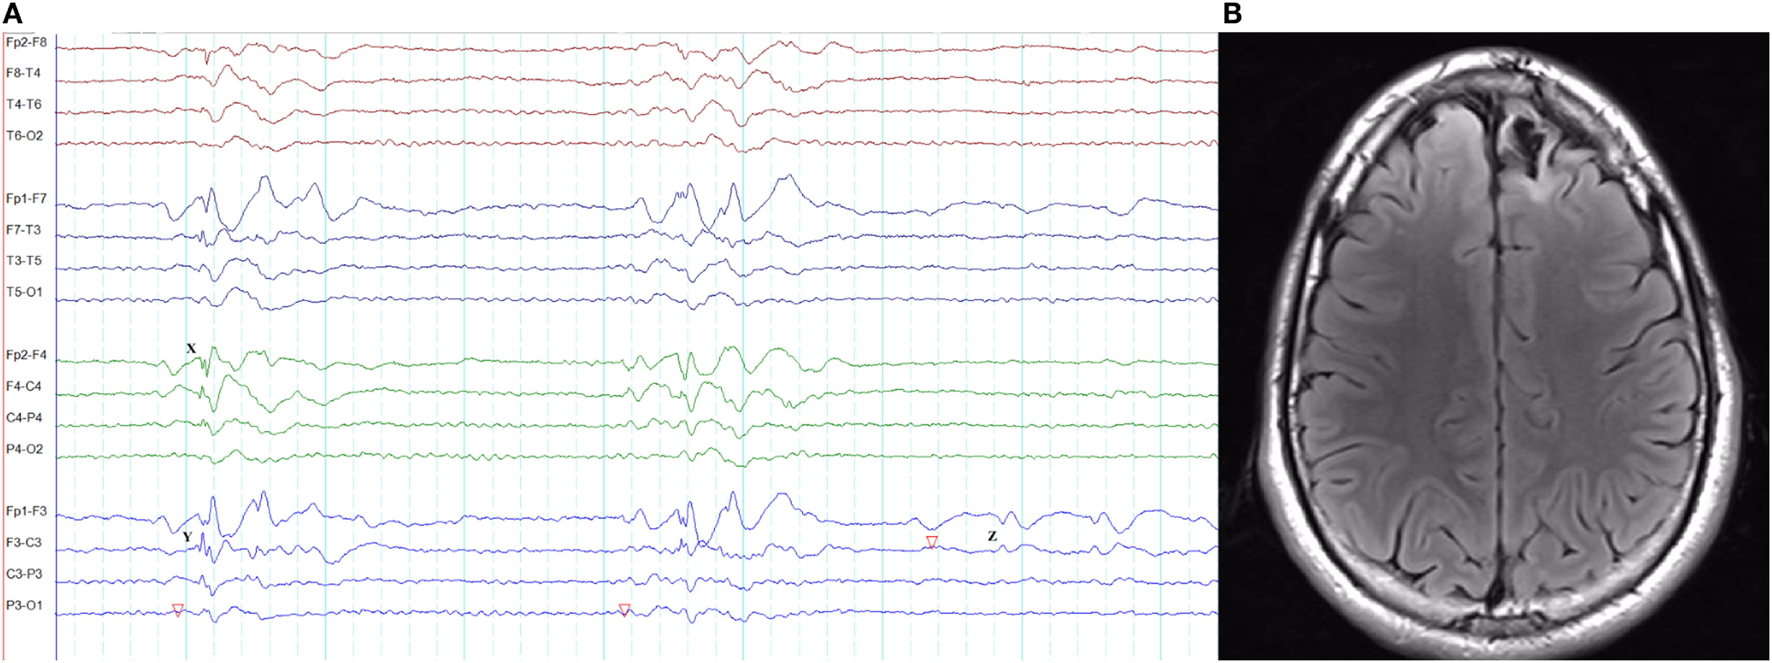

Figure 3

Epileptiform K-complexes and sleep spindles in genetic generalized epilepsy. (A) Polyspikes overlap with a K-complex at X. (B) A burst of generalized spike-wave discharges (Y) in the midst of a sleep spindle.